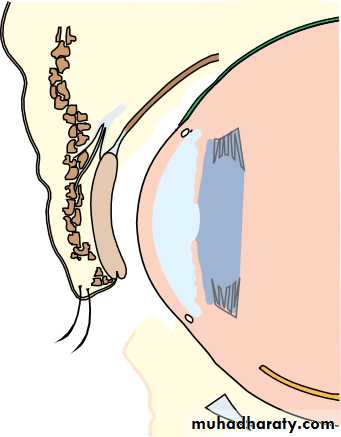

• ORBIT (Fig. 1.2)

• The eye lies within the bony orbit whose structure is shown in Fig. 1.2.The orbit has the shape of a four-sided pyramid. At its posterior apex is the optic canal which transmits the optic nerve to the brain. The superior and inferior orbital fissures allow the passage of blood vessels and cranial

• The anatomy of the orbit.• nerves which supply orbital structures. On the anterior medial wall lies a fossa for the lacrimal sac. The lacrimal gland lies anteriorly in the superolateral aspect of the orbit.